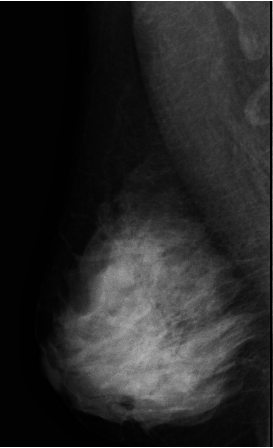

유방암 검사 비용은 보통 유방촬영(영산 진단)과 유방초음파(초음파 진료) 두 가지입니다.

유방초음파는 초음파 검사 시 병원마다 약간의 차이가 있지만 기본 10만 원부터 시작하며 보험 미적용 대상입니다.

하지만 초음파 검사 비용에 건강보험을 적용할 시 약 4~8만 원 정도만 내면 됩니다.(60% 수준 감경) 정확한 금액은 의료기관별로 다릅니다.

검사할 때 건강보험 혜택이 적용되는 기준은 따로 있습니다. 우선 가장 보편적으로 사용하는 흑백 영상 초음파 장비는 건강보험이 적용됩니다. 단, 진단 결과에 따라서 양성이냐 악성이냐 여부에 따라 최종 결정됩니다.